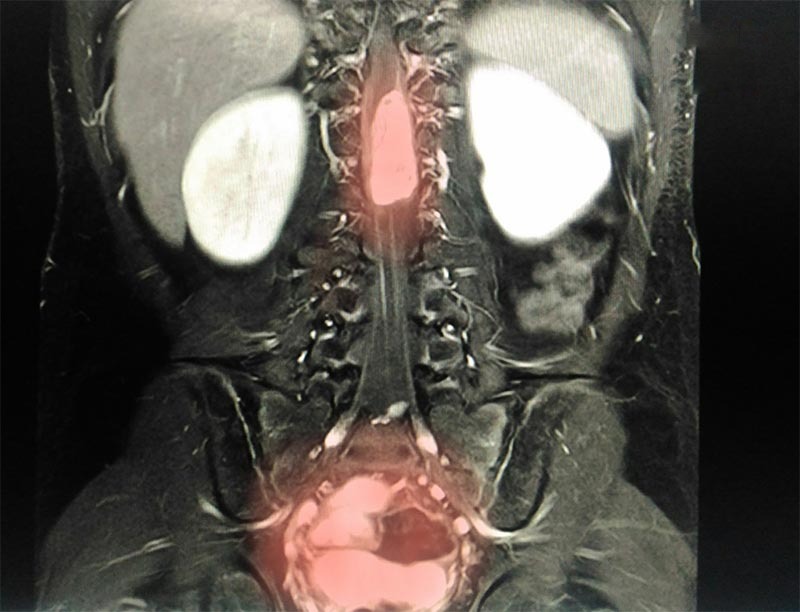

• Chụp MRI (chụp cộng hưởng từ): Qua các triệu chứng và thăm khám lâm sàng, nếu các chuyên gia nghi ngờ nguyên nhân dẫn đến gù lưng là do khối u hoặc nhiễm trùng, nhiễm khuẩn sẽ chỉ định bệnh nhân chụp MRI.